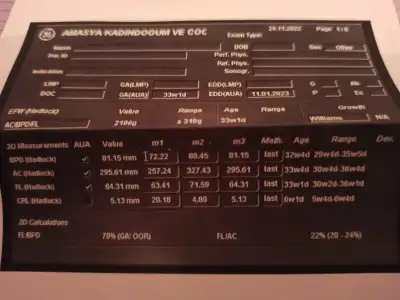

Gözün Aydın canım inşallah bir an önce bebeğinle kavuşup evinize geçersiniz sağlıkla büyüsünSelam kızlar, bugün 37+5ken sezeryanla geldi minik kızım 2880 Gr,49 santimmis, suyum tamamen bitmiş ilginç bir şekilde ,bebeğimin de nefes alış verişi biraz hızlı imiş , doktor biraz rahatlasın diye kuvoze almış , benim uyuşuklugum geçince yanına ineceğim görmek için , ins çabuk toparlar kavuşuruzspinal anestezi ile oldu doğum anı bence çok rahattı bebeğim cikisina şahit olmak çok güzel sesini de duydum orda